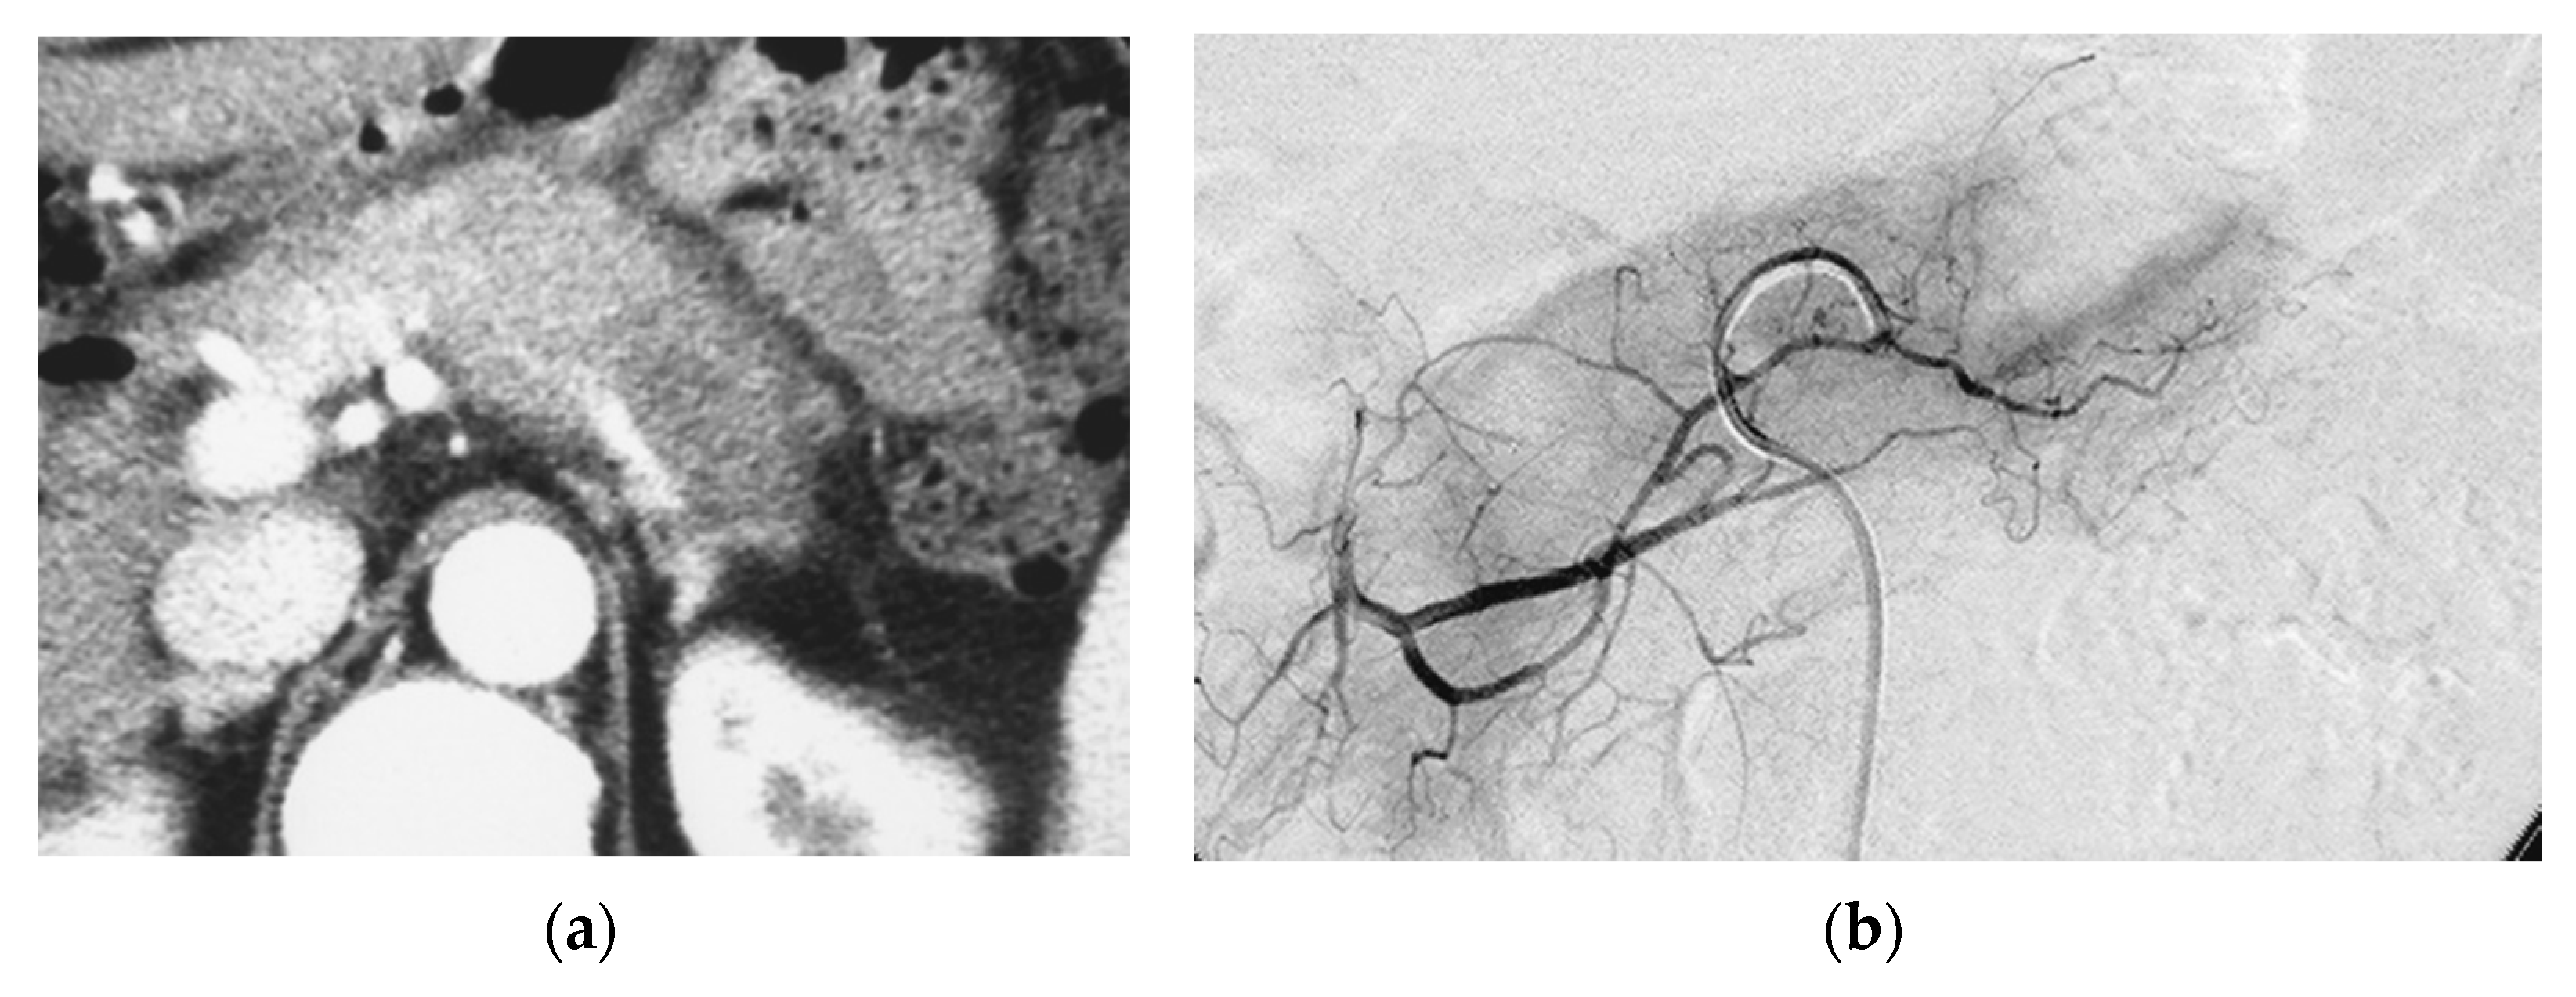

Identifying Supplying Arteries to Pancreatic Cancer

Method of Arterial Administration of Anticancer Agents